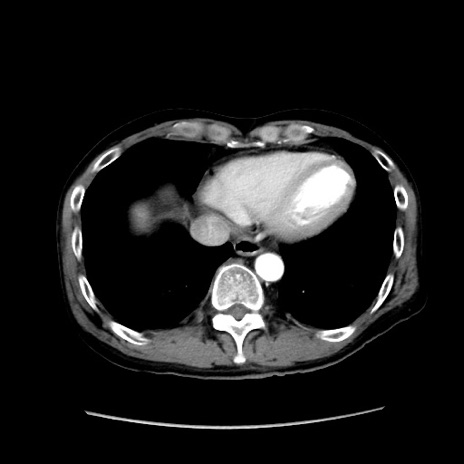

冠状断像

【症例】40歳代 男性

【主訴】腹痛

【現病歴】4時間ほど前に電車に乗車中に臍部上より腹痛出現。徐々に増悪し起立困難となり、救急外来受診。生ものは数日食べていない。今朝お雑煮を食べた。

【身体所見】BT 36.8℃、BP 117/84mmHg、HR 91/min、SpO2 97%、苦悶様、腹部:臍上部広範囲圧痛あり、反跳痛±

【データ】WBC 8100、CRP 0.03